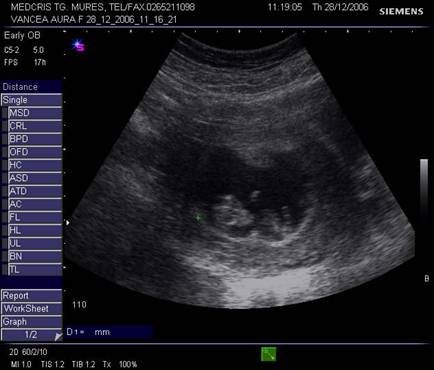

Fig nr. 13. Embrion cu activitate cardiaca, examen Doppler pulsat si Color Flow Map, ritm cardiac de 134 batai pe minut